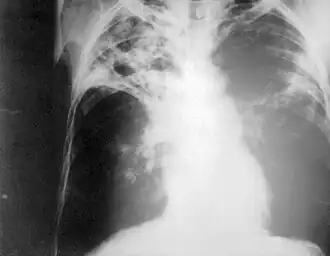

Chest radiography showing advanced bilateral pulmonary tuberculosis. Source: CDC

Purposemass screening for tuberculosis